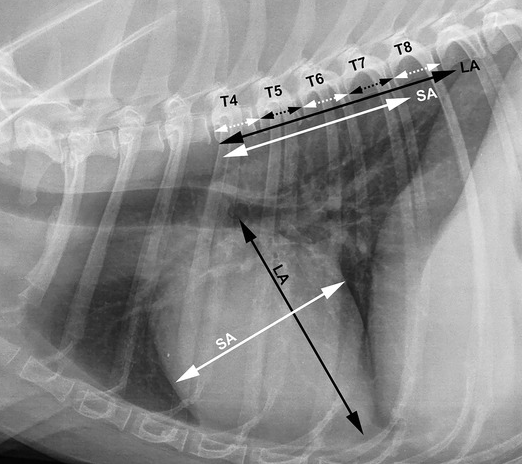

심장의 장축과 단축을 각각 척추체의 길이로 치환하는게 아니라

두 숫자의 크기를 합하여 척추체 4~8번을 각각 나눴을때 VHS와 어느정도 상관성을 갖는가에 대한 논문이다.